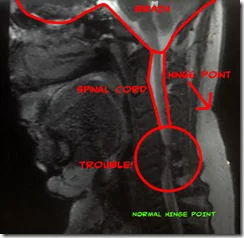

After fighting the NHS for far too many years, even waiting 6 years for an MRI that should have happened at least 4 years earlier if not sooner than that, I underwent a Cervical Discectomy.

It was the culmination of years of bureaucracy and hassles, pain management techniques and drug regimes, understanding and disillusionment (being called a liar and told it’s all in your head is rather deflating!) – but it wasn’t something that we had rushed into. The operation carried risks – let’s be clear about this, I was having surgery on my spine in the cervical region… if something went wrong or a slight slip happened then I faced life as a quadriplegic! As it turned out later, if I hadn’t have fought or if we hadn’t taken the option of surgery then that would have been the end-game anyway as my spinal cord was being compressed by over 50%.

A cervical discectomy, in my case, involved some bone shaving and removing some discs to be replaced by a cage filled with bone, polymer and titanium. So much so that my neck doesn’t hinge at the bottom like most peoples but rather 2-3 inches higher up at the top of my neck.It also makes me my own version of the Bionic Man ![]()

The other area that came up once the experimental MRI results were seen (which wasn’t until after my surgery) was relieving the pressure on my spine so that I could face a future without fear of losing the use of my arms and legs.

The op has managed to relieve most of the pressure on my spinal cord, although there is one area where it is still compressed on one side, but the delays in getting the surgery have meant that the damage is most likely permanent.

Now, do you want to see something cool? Here’s a quick snapshot, rather shaky I’m afraid, of my dynamic MRI. with a piccy above it so you can understand what you are seeing… enjoy!